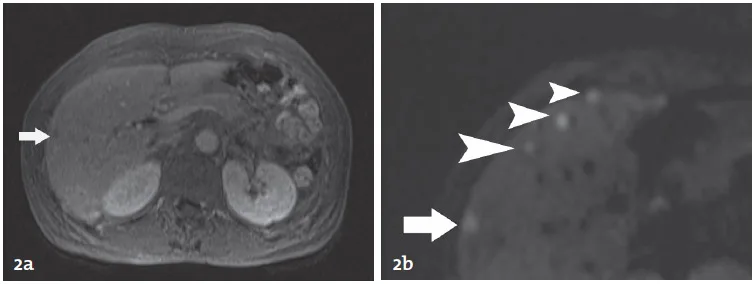

Les produits de contraste hépato-­spécifiques incluent le Gadolinium EOB-DTPA (Primovist, Bayer) et le Gadolinium BOPTA (Multihance, Bracco Italie). Seul le Gd-BOPTA est actuellement disponible en France. Ces deux agents de contraste sont capables de fournir des images de rehaussement vasculaire et intertitiel identiques aux chélates de Gadolinium extra-cellulaires, mais présentent la propriété supplémentaire d’être captés par les hépatocytes par l’intermédiaire des récepteurs OATP exprimés à la surface des hépatocytes avant d’être en partie excrétés dans la bile au travers des canaux canaliculaires MRP2 (Fig. 3). Cette phase hépato-spécifique, qui reflète à l’échelle cellulaire la balance de concentration entre récepteurs OATP d’entrée et MRP2 de sortie, est observée 20 min après l’injection pour le Gadolinium EOB-DTPA, et une heure après l’injection de Gadolinium BOPTA [18–20].

Figure 3. Représentation schématique de la distribution hépatocytaire des produits de contraste dits « hépatospécifiques ».